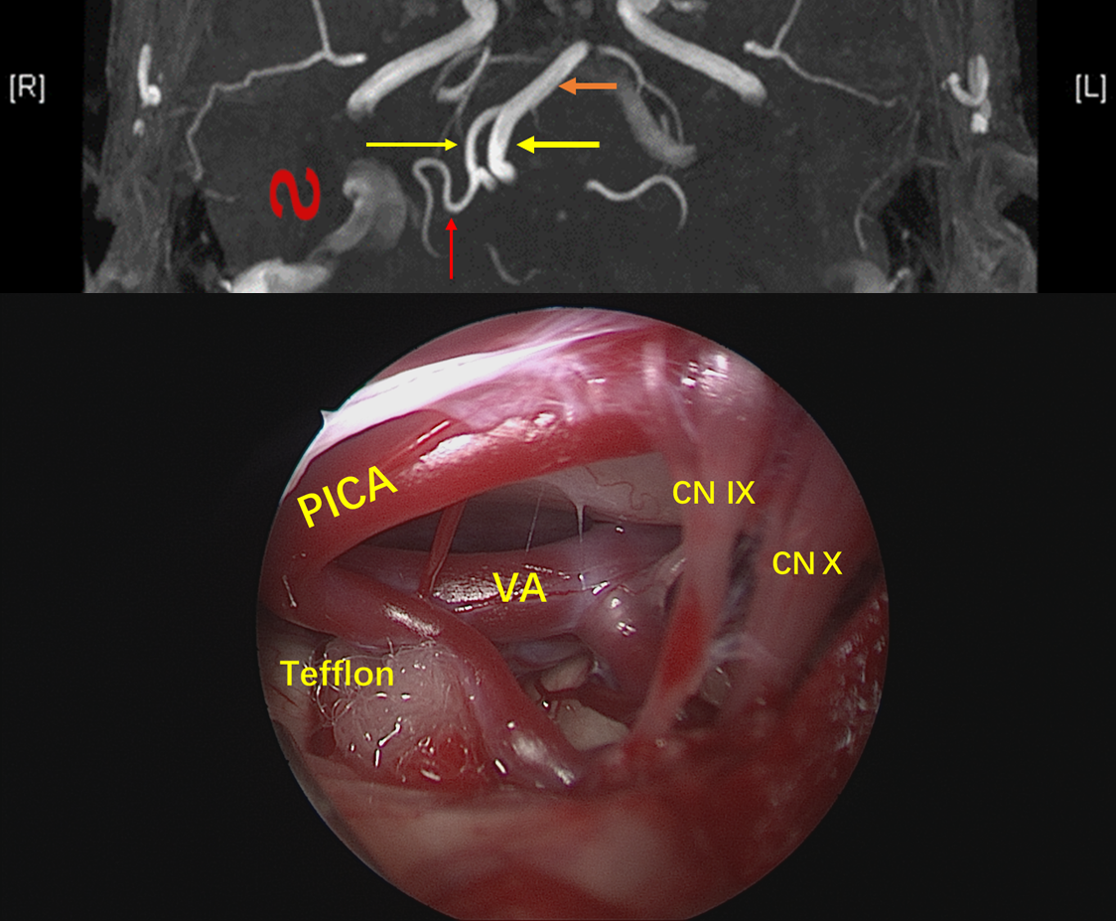

CASE2:右侧面肌痉挛(PICA)

陈**,66岁女性

阵发性右颜面部不自主抽动20年

3D-TOF序列提示椎基底动脉迂曲,偏向右侧,小脑后下动脉PICA从劣势椎动脉发出,于上下各成一袢,最后绕回下方,呈“S”型。

TOF序列及FIESTA序列可见PICA在下方的第一个弯曲与面听神经关系密切。

镜下:从面听神经与后组颅神经之间观察迂曲的小脑后下动脉。

神经内镜抵近观察,与术前影像一致,PICA从VA发出后于下方呈袢,压迫面神经出脑干处。

Tefflon垫绵充分减压。再次观察,PICA如我们所见,迂曲呈“S”型,再于后组颅神经后方(手术视角)绕回,与小脑后下动脉走行特点相吻合。

术后恢复良好,未再抽搐。